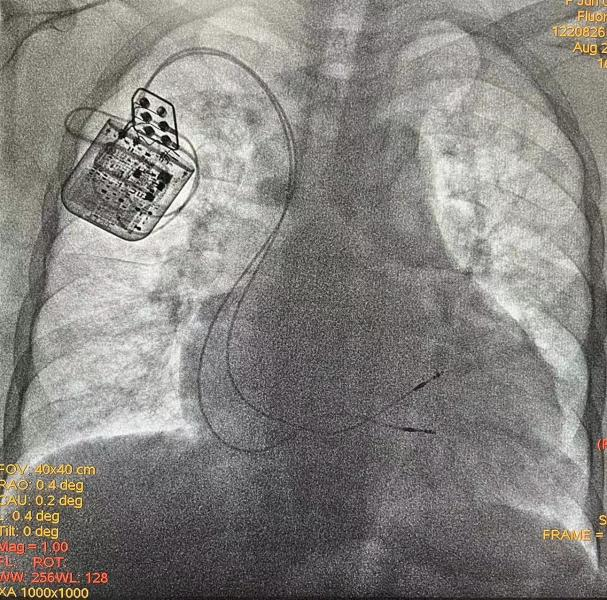

经与患者及家属充分沟通后,手术由何榕、刘元伟主刀,术中将两根导线进行固定,连接至植入式脉冲发生器,脉冲即刻稳定发放,手术顺利结束。术后,患者自觉气短症状减轻明显,出院复查显示左室射血分数已提升至31%,目前已顺利出院。